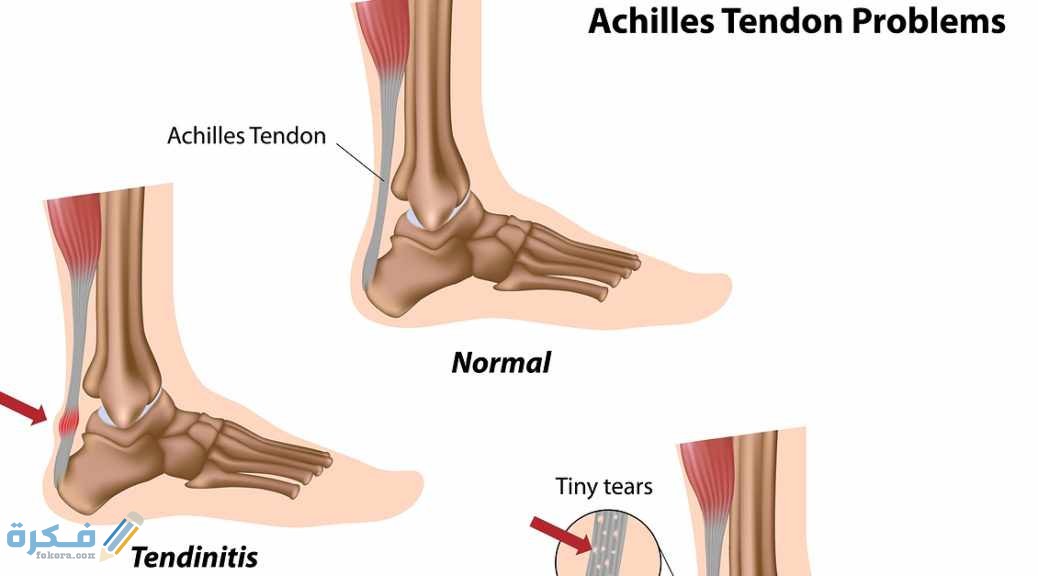

أكمل القراءة »كم يستمر التهاب الأوتار وطرق علاجه من خلال موقع فكرة التهاب الاوتار واحد من الامراض الشائعه لدي الرياضيين وكبار السن…